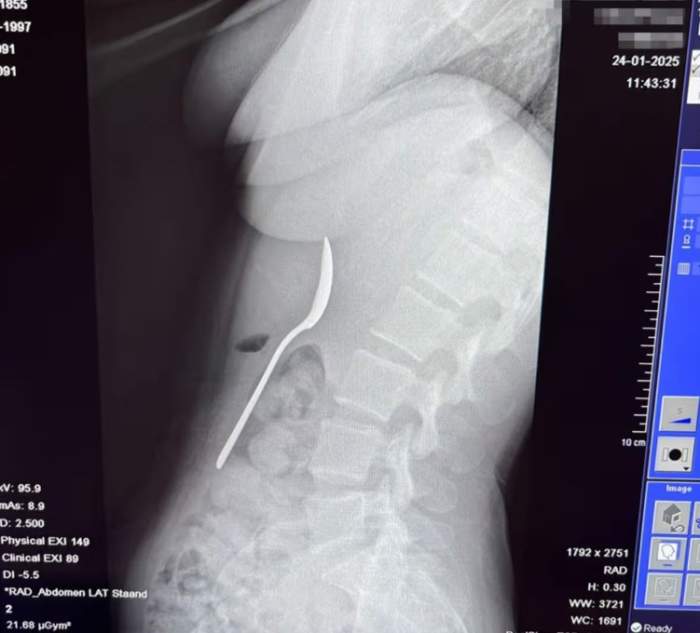

Tinerei i-au scos lingura din stomac două zile mai târziu

Tânăra povestește că a trecut prin momente dificile în cele două zile până la intervenție.

Ustensila i-a fost îndepărtată sub anestezie locală, fără să fie nevoie de o intervenție chirurgicală deschisă.

Câteva ore mai târziu după intervenție, tânăra a fost externată și a început să se recupereze rapid. Spune că a avut unele dureri în gât din cauza leziunilor esofagului, câteva episoade minore de sângerare gastrică și stomacul sensibil pentru o perioadă, însă nu a avut leziuni permanente.